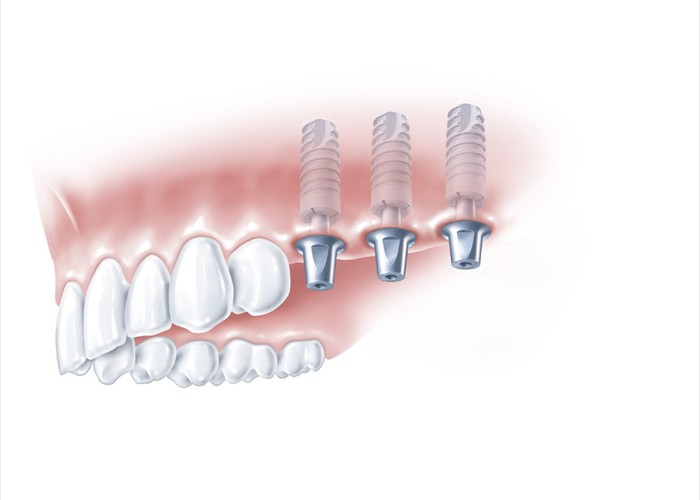

Derselbe Fall mit Implantaten für eine festsitzende Lösung

Derselbe Fall mit Implantaten für eine festsitzende Lösung